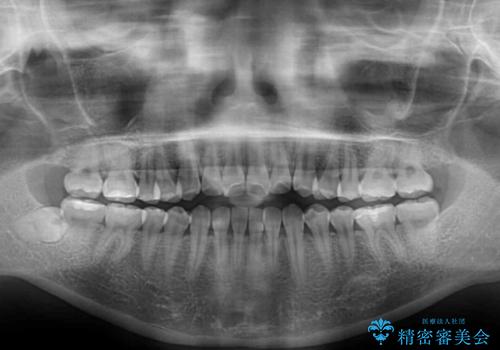

舌の突出癖により上下の前歯は非接触となっている状態でした。

舌のトレーニングを行わないと上下前歯の接触達成は困難であるため、トレーニングをしっかりと行っていただきながら、治療を進めて行くこととしました。

上下左右の第一小臼歯4本を抜歯し、ワイヤー装置にて矯正治療を行うこととしました。